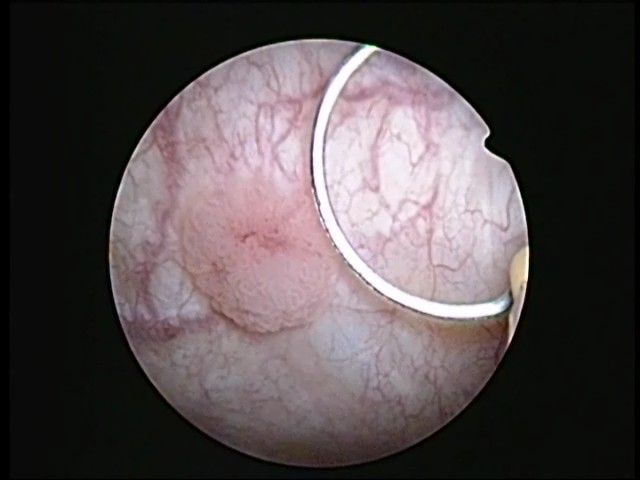

Un polype est un cancer de vessie (preuve apportée par l’analyse anatomopathologique) sauf très rares cas.

Ce polype est soit SUPERFICIEL = n’envahit pas le muscle vésical, soit PROFOND = envahit le muscle vésical.

La cytologie urinaire, l’échographie, l’uroscanner posent le diagnostic. La cystoscopie et enfin la résection (exérèse) de la lésion le confirment.

Pour les polypes superficiels, la résection transuréthrale de vessie ou RTUV permet l’exérèse du polype

Mr Mor lio 022 0002cancer de vessie superficiel vu en cystoscopie en lumière blanche